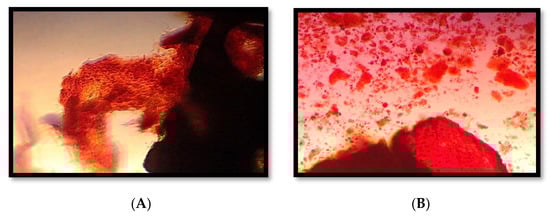

2.4. Mineralization Assessment

3.2. Outcomes of the Mineralization Assessment